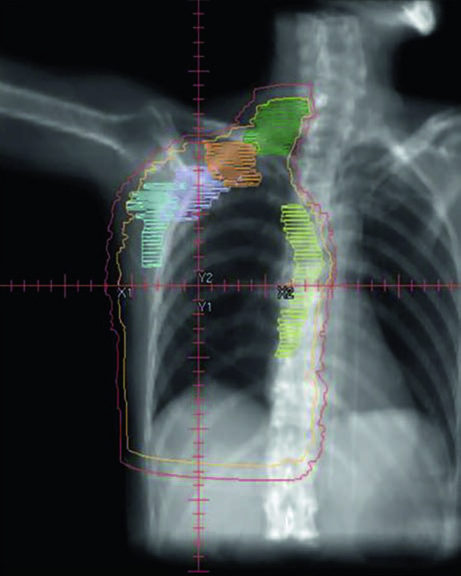

Unreconstructed Right Chest Wall

In the post-mastectomy setting without reconstruction, the chest wall constitutes the primary CTV alongside the nodal volumes. Figures 12.1 and 12.2 (coronal and sagittal) and Figure 12.3 (axial slices) illustrate how the contours are distributed: the PTV follows the curvature of the remaining chest wall, with nodal stations contoured contiguously.

Without a prosthesis or expander in the field, planning is more straightforward. The chest wall is relatively flat, allowing tangents with conventional angulation. The main challenge lies in ensuring uniform skin coverage and adequate retrosternal coverage where the IMN reside, without excessive ipsilateral lung dose. The absence of prosthetic volume reduces dosimetric complexity but does not eliminate the need for optimization — especially at the junction between tangential and supraclavicular fields.